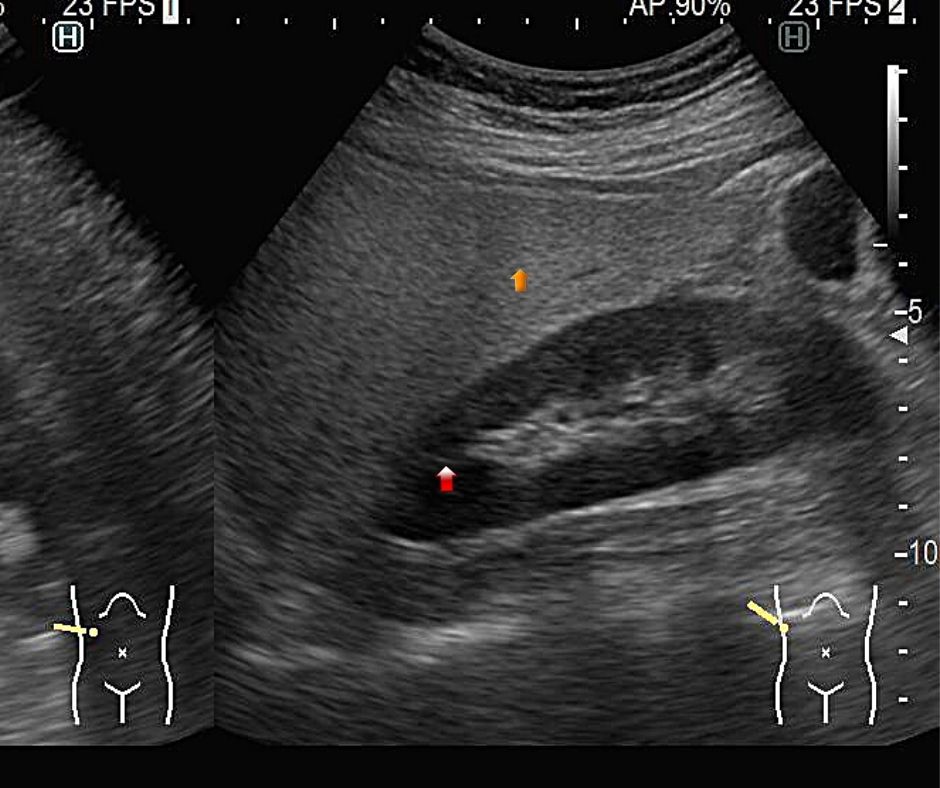

肝臓を占拠する!!パート1~できもの 悪くないもの 」腹部超音波検査 Vol.3 – みどり病院神戸市、明石市、循環器、透析。